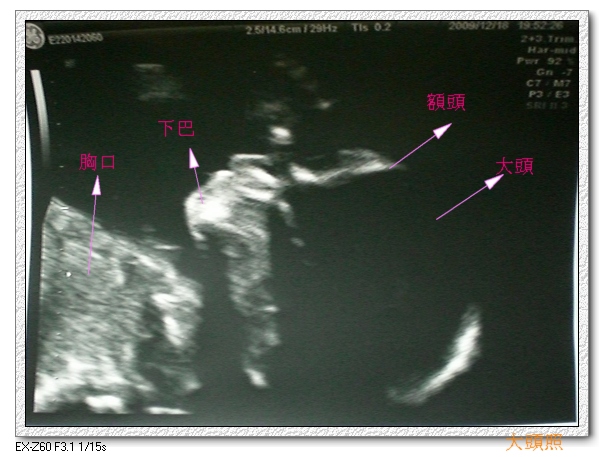

從多錢的頭圍、肚圍、四肢、耳朵、嘴唇、生殖器與蛋蛋、

到腦部、各內臟器官的狀況、血流狀況都檢查過ㄧ次。

兩隻手各五個手指頭、兩隻腳各五個腳指頭、兩個耳朵、嘴唇沒有兔唇,

內臟器官也都有,血流方向也對了,

多錢仔跟他爸爸ㄧ樣很愛把手放再頭臉附近,頭還一直動來動去,

讓3D都抓不准他的長相,好可惜唷!